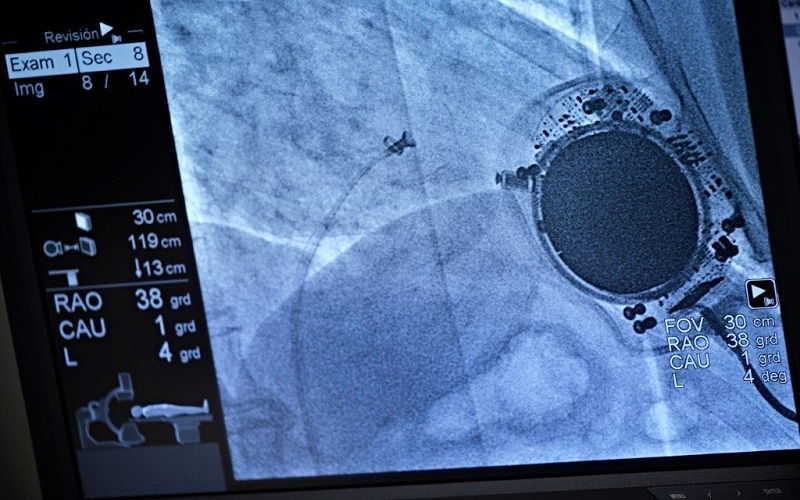

21 de enero de 2019

Prevención del ictus a través de una nueva técnica

Se basa en la introducción de un dispositivo en la orejuela auricular izquierda para que no se ocasionen allí los trombos

Con el nombre de "cierre percutáneo de orejuela izquierda" se conoce al nuevo tratamiento de prevención del ictus. Esta técnica se dirige a personas que no pueden tomar anticoagulantes orales, como las pastillas de Sintrom, y que sufren una...